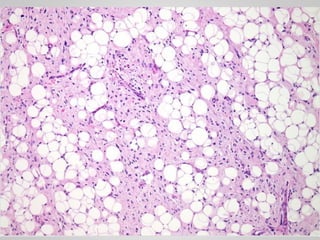

• Well-differentiated liposarcoma

• Adipocytes with scattered atypical spindle cells

• 12.

LIPOSARCOMA • One ofthe most common sarcomas of adulthood • People in their 50s to 60s • Deep soft tissues of the extremities and in the retroperitoneum • Amplification of MDM2 gene

• 13.

• Well-differentiated liposarcoma •Adipocytes with scattered atypical spindle cells • Myxoid liposarcoma • Abundant basophilic extracellular matrix, arborizing capillaries and primitive cells at various stages of adipocyte differentiation • Pleomorphic liposarcoma • Sheets of anaplastic cells, bizarre nuclei and variable amounts of immature adipocytes (lipoblasts).

• #15 Well-differentiated liposarcoma